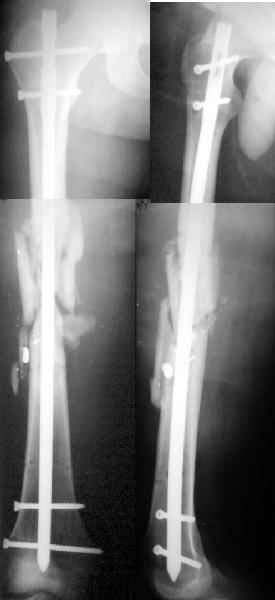

A male 25 y.o 3 months ago was fixed by the Ilizarov fixator applied somewhere else for comminuted femoral fracture after low velocity shotgun wound. Wound healed without infection. Knee ROM is only 20 degrees to date. Recent xrays attached. I think about conversion to an intramedullary nail at least to improve knee function.

Our modest exchange experience was more optimistic so i proceed with the nailing (UFN 11 mm) before i read answers :-(

So 5th day i am about a nervous breakdown. After the surgery except the cold shower from the group a laboratory report was received that he is also HIV and hep. C infected. So i keep fingers crossed. I attached xrays and current view of the leg. All looks calm at the moment... How long to proceed with antibiotics and heparin?

The patient feels fine, no fever, ambulates with crutches, knee ROM is 0/90, and he is going to leave for home tomorrow.